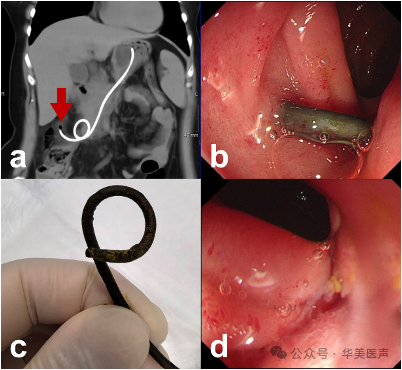

图1 a. 胰腺炎伴胰腺假性囊肿延伸至右侧下盆腔。b. 3D 计算机断层扫描(CT)重建示胃内引流管的猪尾端与右半结肠(箭头)密切相关,后曲段与十二指肠相邻(三角形)。

CT平扫和3D重建显示猪尾导管远端似乎移位进入结肠肠腔,行胃镜检查,起始部导管竟也穿破十二指肠壁。

幸运的是,我们仅仅只使用异物钳便成功取出引流管,引流管末端粪渍黏附也证明了结肠瘘的存在,并且镜下十二指肠黏膜穿孔处仅见充血,无活动性出血(图2)。

图2 a. 3D CT重建显示支架的远端弯曲端已进入结肠腔。(箭头)b.可以看到引流管穿过十二指肠的降段部分。c.淡黄色的粪便附着见于引流管的远端(猪尾端)。d.十二指肠显示黏膜充血,无出血。